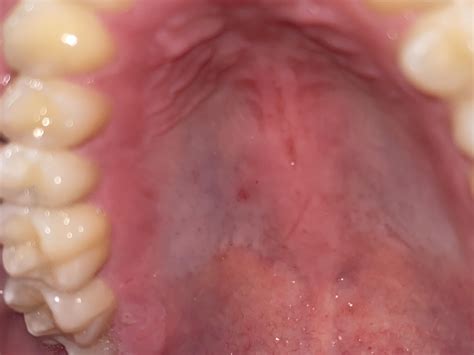

The roof of the mouth, also known as the palate, is divided into two parts: the hard palate and the soft palate. The hard palate is the bony front portion, while the soft palate is the muscular back portion. The hard palate is covered by a mucous membrane, which can sometimes develop discolorations, including a white roof of mouth.

• Leukoplakia: This condition involves thick, white patches that can develop on the roof of the mouth and other areas inside the mouth. It is often painless but can be a sign of precancerous changes.

• Lichen Planus: This is an inflammatory condition that can cause white lines or patches on the roof of the mouth and other mucous membranes.

• Oral Lichen Planus: This is an inflammatory condition that can cause white lines or patches on the roof of the mouth and other mucous membranes.

Symptoms of a White Roof of Mouth

The symptoms of a white roof of mouth can vary depending on the underlying cause. Common symptoms include:

• White patches or discoloration on the roof of the mouth.

• Redness or inflammation in the mouth.